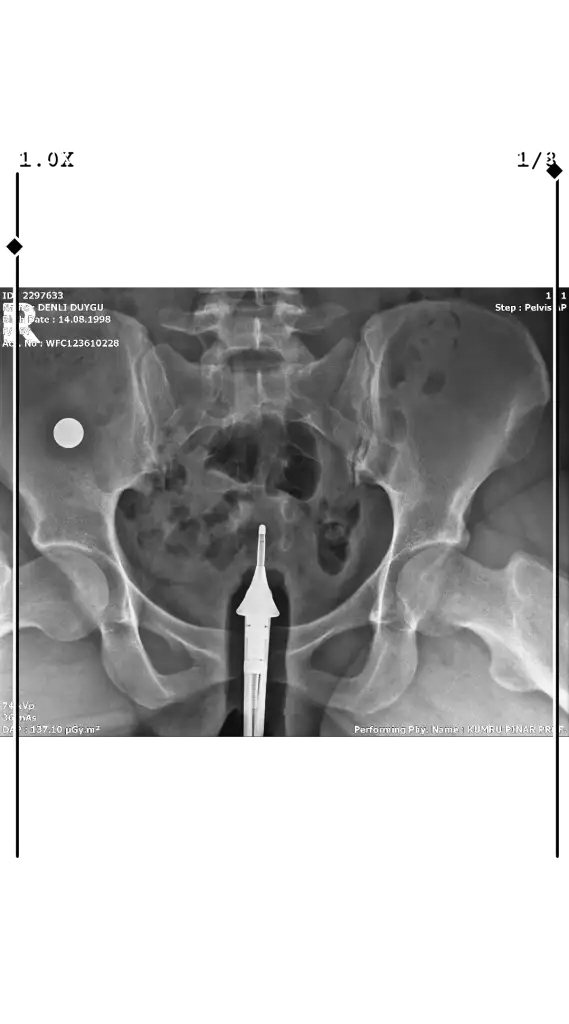

Sadece bu görüntü mü varRahim filmim bu şekilde henüz yorumlanması hiç iç açıcı görmüyorum yorumlar mısınız lütfen

Eki Görüntüle 3503606

Bunlar da varSadece bu görüntü mü var

Tüplerden dağılım olmamış gibi duruyor tıkalı sanırımBunlar da var

Görsellerde adınız çıkmış bilginiz olsun, rahminiz arkaya doğru mu neden o şekilde çıkmış sonuçlarda dağılım olmuş demiş ama görselde yokYorumlar mısınız lutfen

Herşey olması gerektiği gibi kameradan dolayı farklı çıkmış dediGörsellerde adınız çıkmış bilginiz olsun, rahminiz arkaya doğru mu neden o şekilde çıkmış sonuçlarda dağılım olmuş demiş ama görselde yok